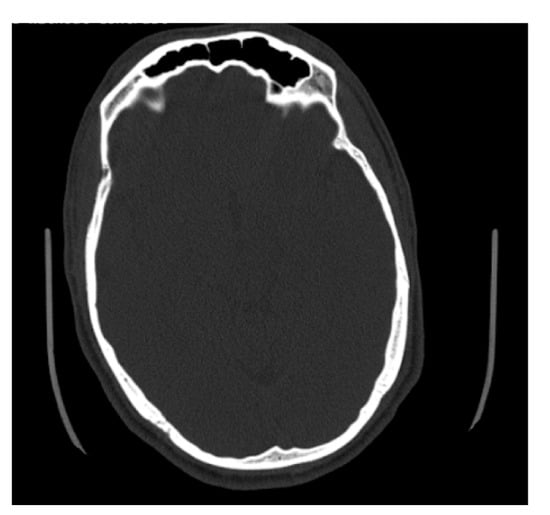

2.2. Dimensional Analysis

3.2. Dimensional Variation Analysis